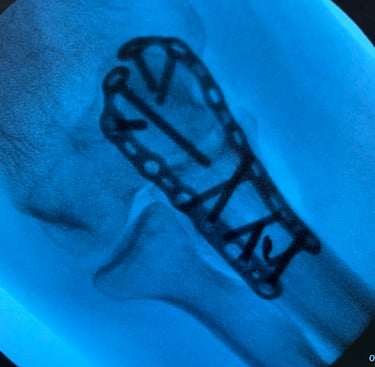

Mi occupo del trattamento delle principali patologie del gomito, tra cui tendiniti (come epicondilite ed epitrocleite) e traumatologia del gomito. Eseguo inoltre il trattamento chirurgico delle rotture del tendine distale del bicipite, con tecniche finalizzate al recupero della forza e della funzionalità dell’arto superiore.